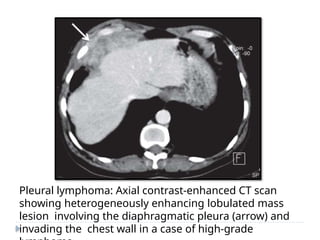

LYMPHOMA

⚫ Both hodgkin’s and non

hodgkins lymphoma can

involve the pleura.

⚫ IMAGING :

⚫ Pleural effusion

⚫ Pleural nodules

⚫ Focal or diffuse pleural

thickening

(circumferential

thickening is less

common).

⚫ Homogeneous contrast

enhancement

⚫ Associated with

Pleural lymphoma: Axial contrast-enhanced CT scan

showing heterogeneously enhancing lobulated mass

lesion involving the diaphragmatic pleura (arrow) and

invading the chest wall in a case of high-grade

PLEURAL METASTASES

LYMPHOMA ⚫ Both hodgkin’sand non hodgkins lymphoma can involve the pleura. ⚫ IMAGING : ⚫ Pleural effusion ⚫ Pleural nodules ⚫ Focal or diffuse pleural thickening (circumferential thickening is less common). ⚫ Homogeneous contrast enhancement ⚫ Associated with

• 109.

Pleural lymphoma: Axialcontrast-enhanced CT scan showing heterogeneously enhancing lobulated mass lesion involving the diaphragmatic pleura (arrow) and invading the chest wall in a case of high-grade